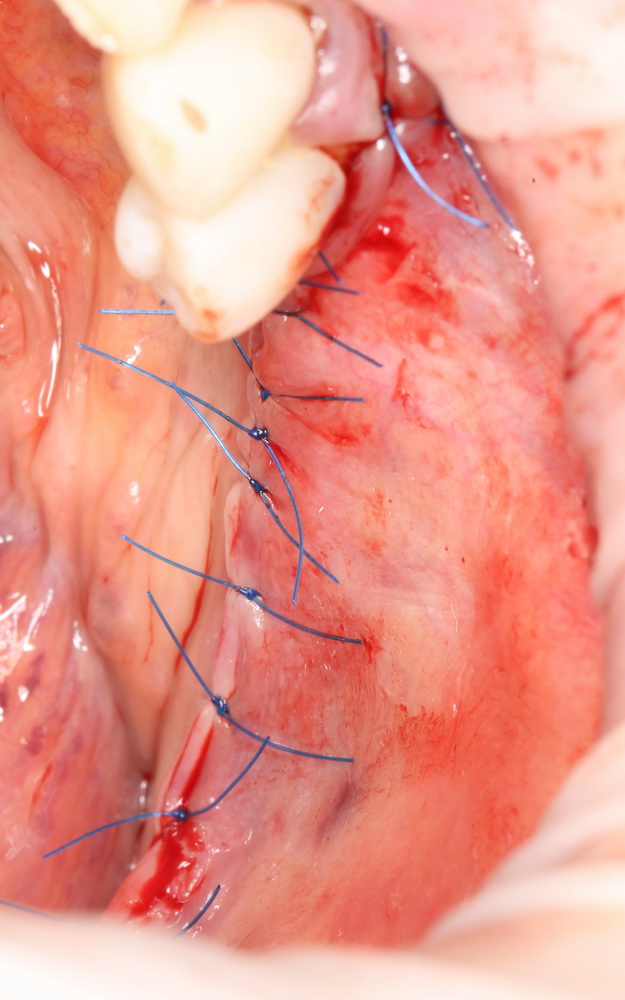

Ну и швы. Последнее и, пожалуй, самое важное. Никаких викрилов, никаких излишних натяжений, максимум герметичности:

Критическое место — рядом с четвертым зубом. Там нужно десять раз проверить и, при необходимости, наложить дополнительные лигатуры.